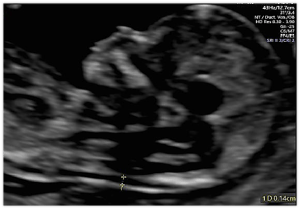

Cerebellar View

Above. The cerebellar view is axial oblique with rotation of the transducer from the thalamic view to the cerebellum, while obtaining a view of the central cerebellar echogenic vermis. This view allows visualization of the cerebellum and cisterna magna (posterior fossa).

Cerebellar Measurements

Above. The cisterna magna or posterior fossa measurement is taken as illustrated from the outer aspect of the cerebellar vermis to the internal side of the occipital bone, and is normally between 2 mm and 10 mm in depth. The transcerebellar diameter is also measured as illustrated from outer to outer aspect of the cerebellum and varies by gestational age. Note the box like cavum septi pellucidi (CSP) which can also be seen with the cerebellar view.